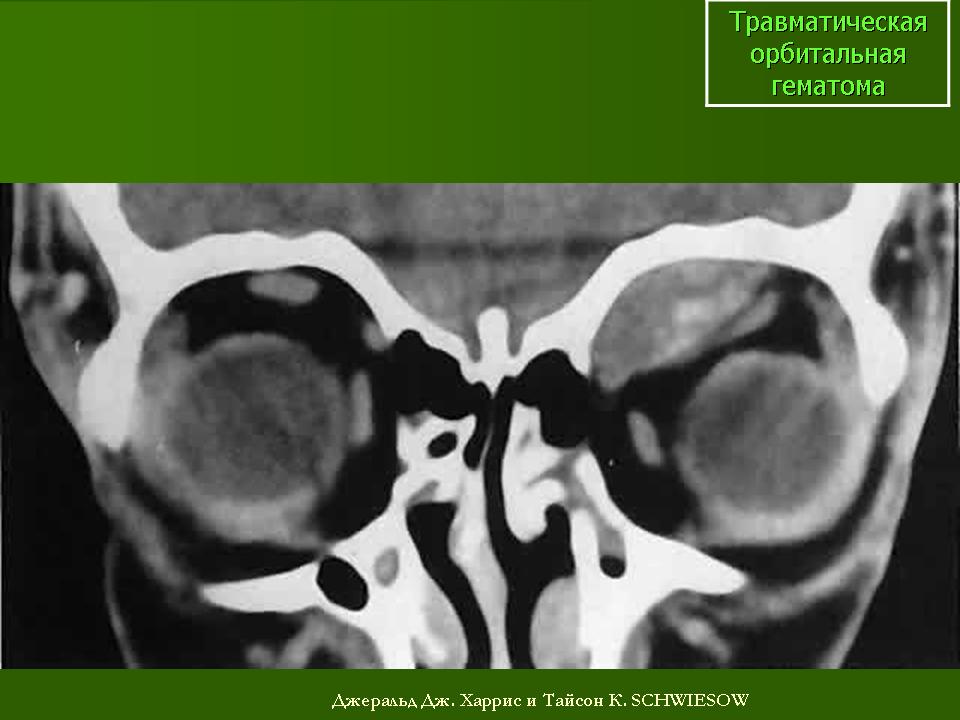

Экзофтальм, как правило, является следствием ретробульбарных гематом. Результаты измерений величины смещений глазного яблока используются для расчетов степени необходимой в последующем репозиции глазного яблока.

Выделяют два типа. Первые – это практически обычные гематомы. Они имеют характерную овальную форму, располагаясь в полости глазницы чаще всего в виде одиночных кровяных сгустков. Плотность этих гематом приближается к плотности свернувшейся крови и варьирует от 40 до 75 НU.

Кровоизлияния второго типа проявляются по типу множественных мелких фокусов уплотнений на фоне глазничной клетчатки, возникших вследствие пропитывания (имбибиции) ее кровью. На компьютерных томограммах ретробульбарная клетчатка глазницы в этих случаях имеет пятнистый, тяжистый вид. Судить о плотности очагов в силу незначительных их размеров не представляется возможным. Однако общая плотность глазничной клетчатки с отрицательных в норме значений (-)100 – (-)50 НU(жир), повышается до (-)10 – (+)10 НU. Лучше всего внутриглазничные кровоизлияния при КТ визуализируются в аксиальной проекции.